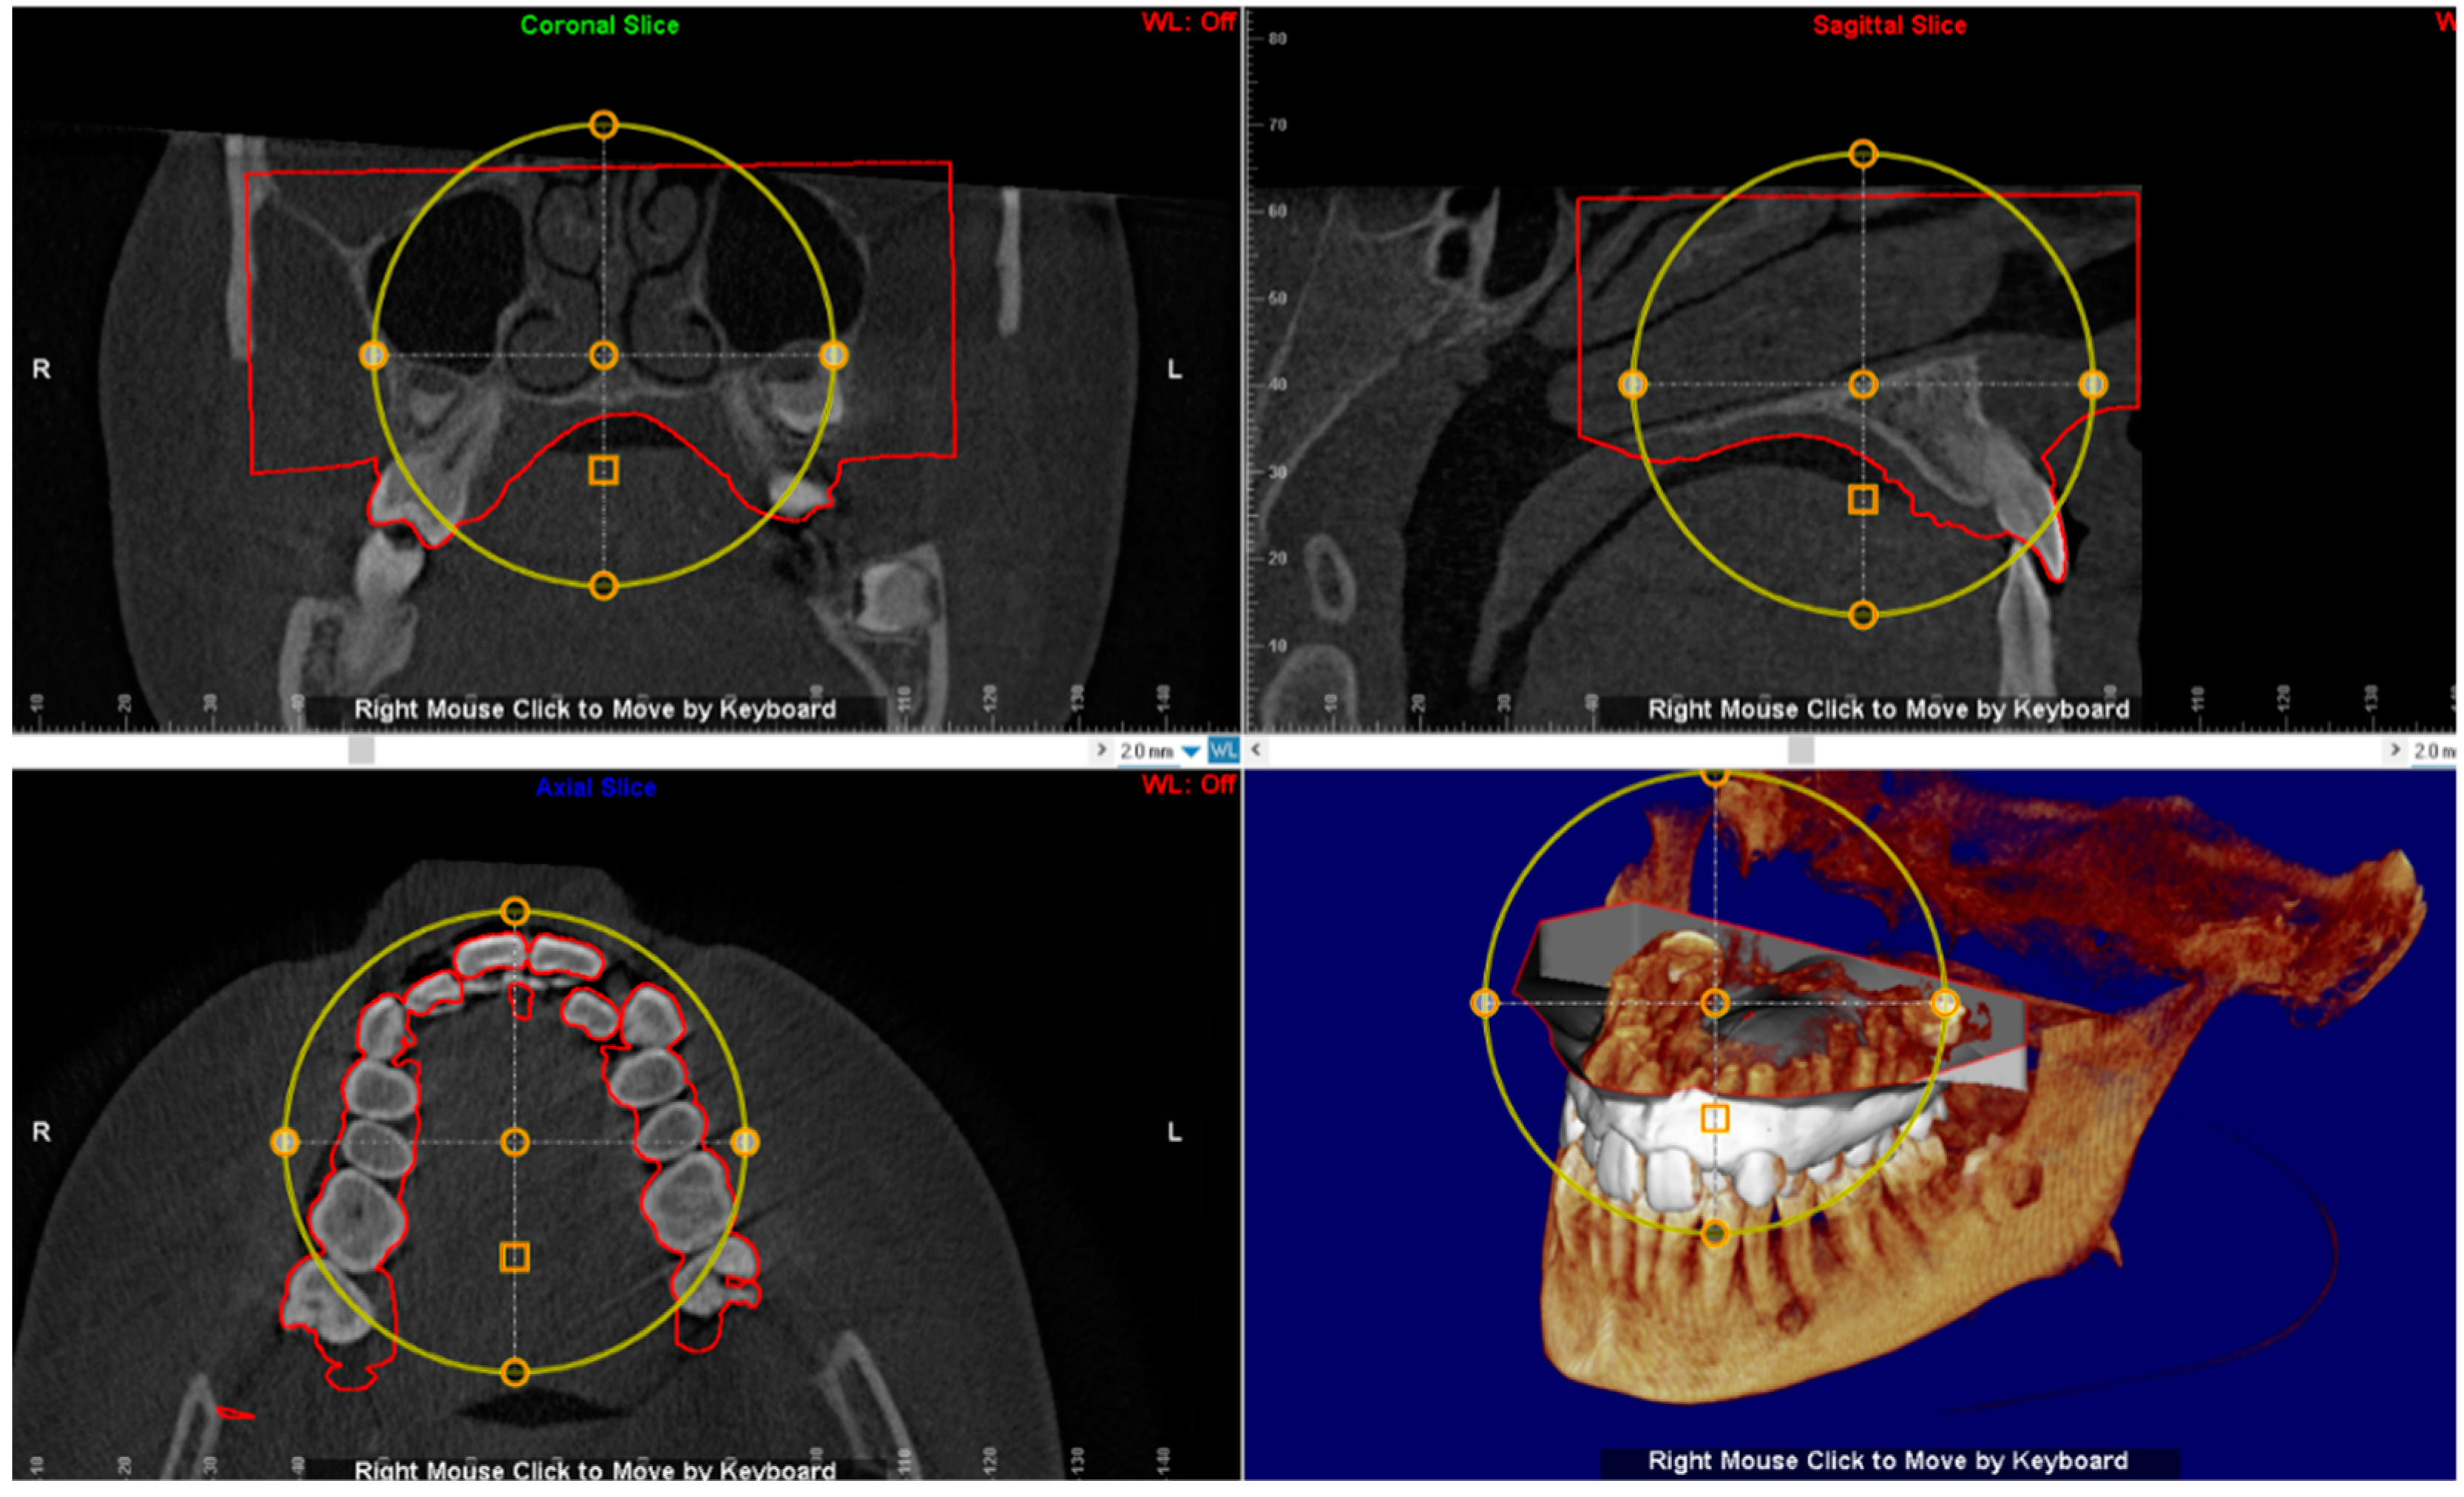

The digital model of maxillary arch is superimposed onto the CBCT DICOM file by selecting specific landmarks along the dental arch in both files (points-based registration), which allows identification of the most suitable vertical and anteroposterior placement of the MSE according to the following goals: bicortical insertion of the miniscrews, close proximity of the lower base of the MSE to the palatal mucosa and central placement of the screw using the nasal septum as visual reference (Figure 4). All these parameters were evaluated in sagittal, coronal, and axial views, and the position of the negative template of MSE was adjusted according to these parameters (Figure 5).

Figure 4.

Superimposition of the digital model of maxillary arch onto the DICOM file for identification of the most suitable vertical and anteroposterior placement of the MSE.

Figure 5.

The position of the negative template of MSE is determined in sagittal, coronal and axial views. See the design of the expander with the four miniscrews that are engaged in the cortical bone of the palate and nasal floor.